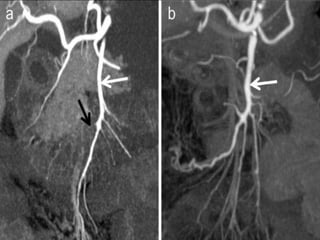

ROLE OF MRI

 True FISP images is used to assess large

 MRI has significant problem in detecting

 Routine use of MRI patients with suspected

Sagittal subvolume and coronal subvolume MIP images show severe stenosis of

the celiac, superior mesenteric and inferior mesenteric arteries.

Sagittal subvolume andcoronal subvolume MIP images show severe stenosis of the celiac, superior mesenteric and inferior mesenteric arteries.